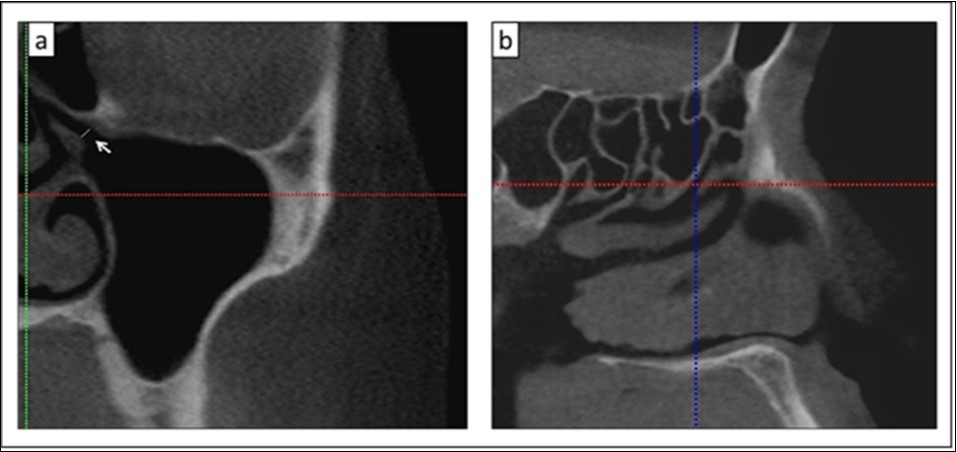

To ensure the accuracy of the anatomical structures depictions, all CBCT examinations were reviewed by a trained oral and maxillofacial radiologist before and after the measurements. The location of the primary maxillary ostium along the course of the hiatus semilunaris was identified. Subsequently, the maxillary sinus ostium diameter (mm) was measured from the inferior uncinate process to the superior lower bony portion of the ethmoidal sinus in the coronal view (Figure 2a). The diameter was measured three times and subsequently the averaged reading was calculated to ensure reproducibility and reduce any subjective bias. The data was recorded and classified according to the ethnic groups and their gender.

Thereafter, the location of maxillary sinus ostium was determined, it was marked with the horizontal and vertical axis lines in the coronal section (Figure 2a). When the sagittal section window was reviewed, the position of the point/marking was determined along the hiatus semilunaris (Figure 2b). The position of the primary maxillary sinus ostium at the hiatus semilunaris were recorded and classified as being in the anterior third, middle third or posterior third of this hiatus. The hiatus semilunaris is interpreted as the opening between the anterior surface of the bulla ethmoidalis and the free edge of the uncinate process 9.

Figure 2.a) Measurement of the primary maxillary ostium between the lower bony part of ethmoid and the uncinate process (white arrow); b) Location of the primary maxillary ostium in the coronal section (a) which is observed in the sagittal section (crosshair lines)